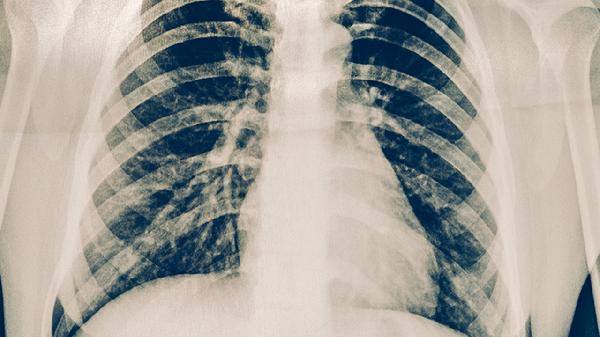

有位呼吸科医生说:"十个肺癌患者里,可能就有一个是厨房油烟害的。"特别提醒40岁以上的家庭主妇/主夫,每年做个低剂量螺旋CT筛查。记住,给家人做饭是表达爱的方式,但千万别让这份爱变成伤害。从今天开始,给厨房来次大扫除吧!